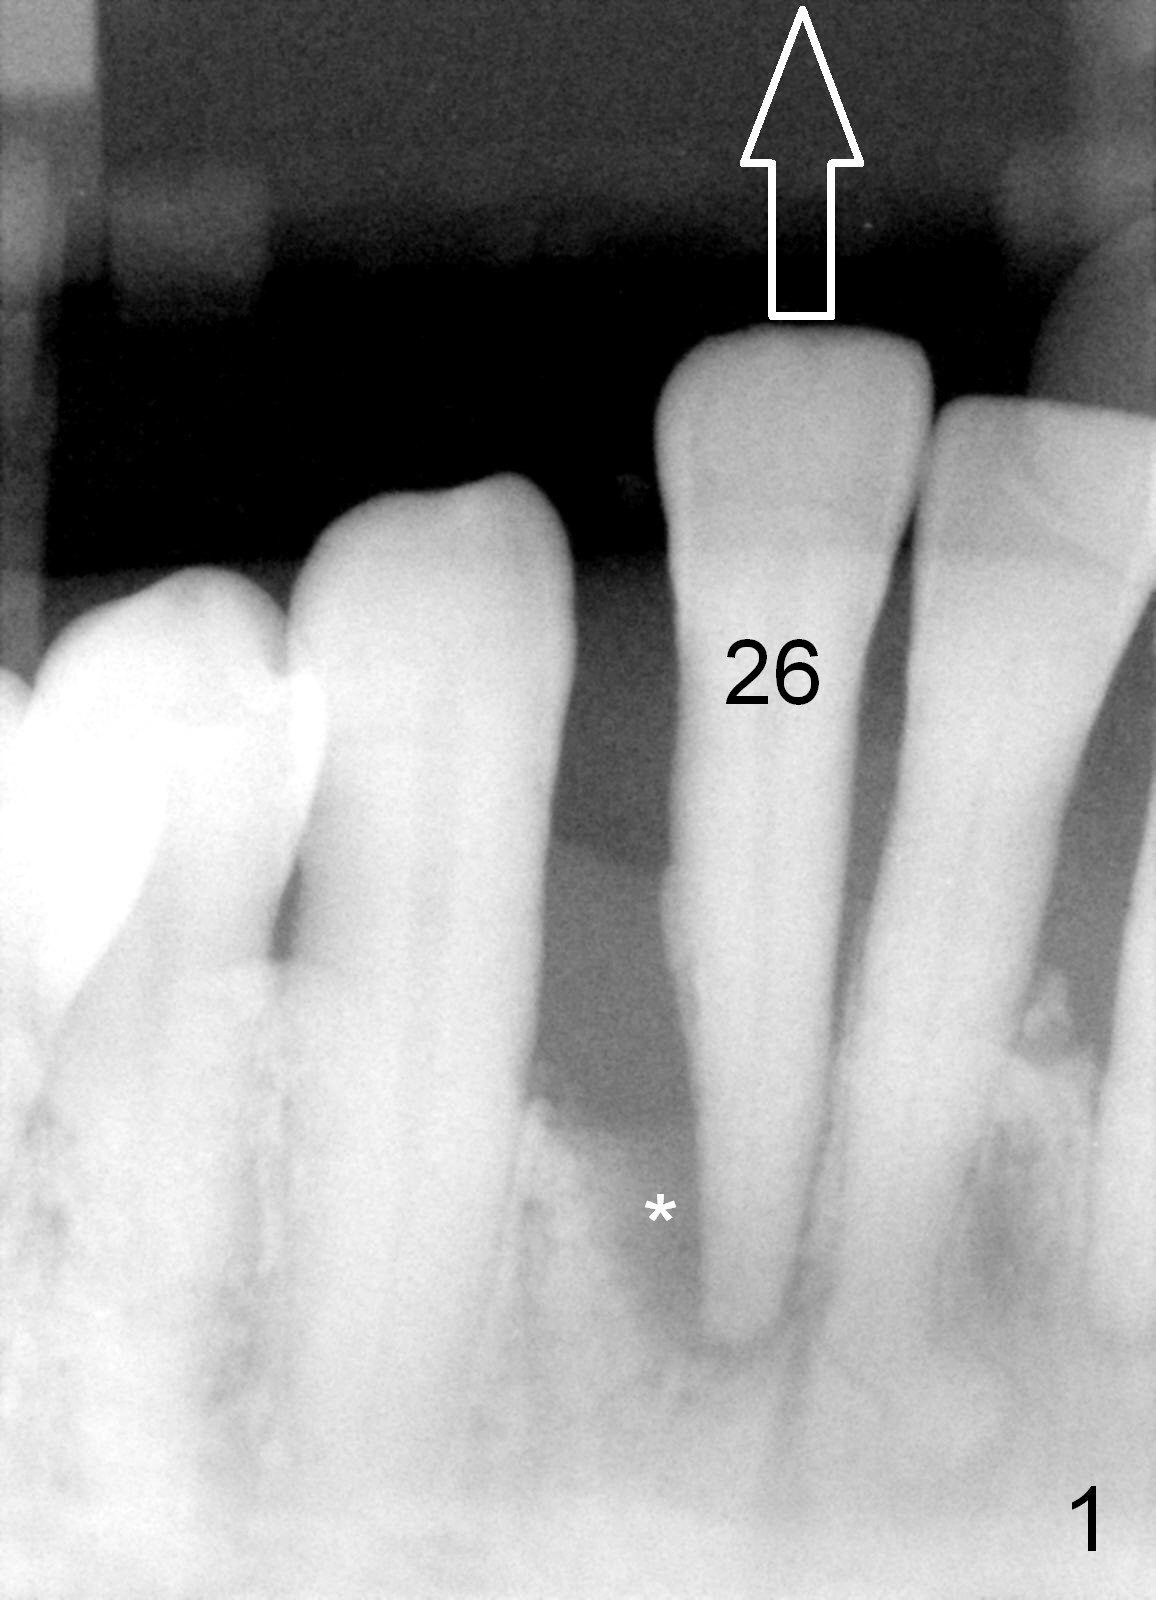

A 65-year-old lady has history of poliomyelitis and use of injection osteoporosis medicine. The tooth #26 is periodontally affected (Fig.1). Since the sensor is not placed deep enough (or there is plenty space above (Fig.1 arrow)), it is difficult to design implant treatment plan (Fig.2). PA has to be taken immediately pre-operatively for precise design.

A tentative design is as follows: a bone-level implant is placed 4 mm subgingival (Fig.3, total gingival height 6 mm (Fig.2)). The cuff will be 4 mm. The most coronal threads are covered by bone graft (red circles).